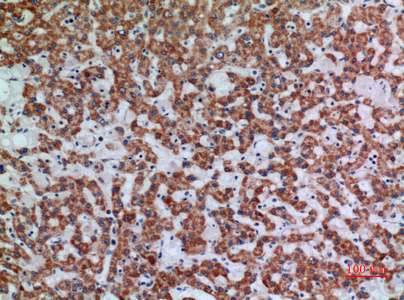

![APAF1 antibody [C3], C-term detects APAF1 protein at cytoplasm in rat liver by immunohistochemical analysis. Sample: Paraffin-embedded rat liver. APAF1 antibody [C3], C-term (GTX101067) diluted at 1:400.

Antigen Retrieval: Citrate buffer, pH 6.0, 15 min](https://www.genetex.com/upload/website/prouct_img/normal/GTX101067/GTX101067_40359_20160713_IHC-P_R_w_23060100_579.webp)